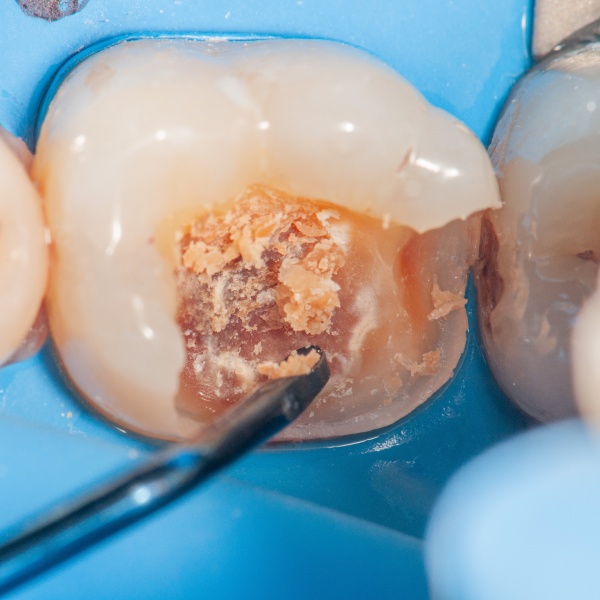

Zákroky se zachováním vitality (hlavně zaměření na pulpotomie)

9. 11.

16:00 - 18:00   MDDr. Jan Kubeček

Co vás v přednášce čeká?

Perforace zubní dřeně při exkavaci hlubokého kazu nebo expozice pulpy po úrazu je situace, která u řady lékařů stále vyvolává obavy. Přitom již neplatí, že obnažená dřeň automaticky znamená nepříznivou prognózu a nutnost endodontického ošetření.

Současné poznatky o biologii pulpy a dostupné terapeutické postupy umožňují v indikovaných případech zachovat vitalitu zubu s vysokou mírou predikovatelnosti. Klíčová je správná diagnostika, indikace a precizní dodržení jednotlivých kroků ošetření.

• Jak se rozhodovat mezi jednotlivými metodami ošetření hlubokého kazu

• Krok za krokem postup ošetření při expozici pulpy v kariézním dentinu i při úrazu

• Jak klinicky odlišit reverzibilně postiženou pulpu od nevratně patologicky změněné

• Jaké materiály zvolit a jak s nimi pracovat pro dosažení optimálního výsledku

Součástí přednášky bude rozsáhlá obrazová dokumentace, včetně videí z konkrétních výkonů a kazuistik.